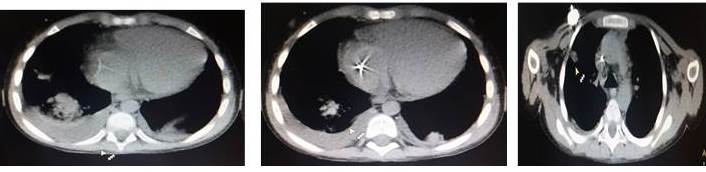

Se trata de escolar masculino de 6 años de edad, natural de Acarigua, (Venezuela) con antecedentes de Diabetes Mellitus Tipo 1 (no tratada), cuya madre refiere inicio de enfermedad actual el día 28/06/2017 al presentar dolor abdominal, difuso, de moderado a fuerte intensidad de carácter urente, concomitante distención abdominal, inapetencia, por lo es evaluado por gastropediatra el cual indica tratamiento sintomático y enema evacuante, para el día 01/07/2017 se asocia a cuadro emesis en n° 03 de contenido bilioso fétido; motivo por el cual es referido a centro hospitalario en San Carlos Cojedes (Venezuela) donde es evaluado y se deciden su ingreso bajo la premisa de: 1. Abdomen agudo inflamatorio 2. Íleo paralítico 3. Hernia inguinal derecha. Es llevado a mesa operatoria, se practica incisión para rectal derecha, apertura de peritoneo, aspiración de líquido claro, localización de masa tumoral, infiltrando techo de vejiga, ciego, epiplón, íleo distal, resección de epiplón (ganglionar) de coloración rosada y de ganglios mesentéricos, tumoración de techo de vejiga de aspecto hemorrágico, necrótico. Para el (25/07/2017) se recibe resultado de biopsia con diagnósticos de inmunohistoquímica para linfoma tipo burkitt cd20+, cd10+ en el 95 % de las células tumorales se le realizan a su vez estudios de extensión (28/07/17) que reportan: TAC DE TÓRAX: foco de condensación en el tercio medio y anterior del pulmón izquierdo y en las bases pulmonares , TAC ABDOMEN Y PELVIS: localización de masa tumoral, infiltrando techo de vejiga, ciego, epiplón, íleo distal, LÍQUIDO CEFALORRAQUÍDEO: sin evidencia de neoplasia, ASPIRADO DE MÉDULA ÓSEA: sin evidencia de neoplasia. En vista de hallazgos se cataloga (ESTADIO II) GRUPO B, por lo que se programa para quimioterapia sistémica: recibe esquema COP (25/07/17) (ciclofosfamida, vincristina,predinisona,e intratecal con metotrexate) con re-evaluación de sitios de enfermedad con respuesta completa, COPADM-1 (ciclofosfamida, adriamicina,metotrexate,vincristina,prednisona) (02/08/17) con una segunda evaluación con respuesta completa, COPADM-2 (vincristina, metotrexate,intratecal con metotrexate e hidrocortisona) (29/08/17): con re-evaluación de TAC de tórax, abdomen y pelvis, sin evidencia de neoplasia. En vista de la respuesta clínica >90 % se programa para su 1er ciclo de consolidación con quimioterapia con CYM el cual cumple por 6 días con excelente respuesta clínica, se le toma líquido cefalorraquídeo posterior a tratamiento con intra-tecal el cual se reporta a los 10 días de su toma positivo para infiltración neoplásico se interconsulta caso con hemato-oncólogos pediatras quienes sugieren intra-tecal triple con (metrotexate-citarabina-hidrocortisona) que se realizó en 3 oportunidades y realizar prueba específica citometría de flujo, la cual se realiza con posterior reportes de líquidos negativos para infiltración neoplásica. En vista de tal escenarios se decide pasar a GRUPO C y recibe su 1er ciclo de quimioterapia con CYVE-1 (citarabina,etopósido y metotrexate) + INTRATECAL el cual posterior a los 10 días en el nadir de su terapia hace toxicidad hematológica con contajes absolutos de neutrófilos <100 por lo recibe antibioticoterapia de amplio espectro. Se le realizan estudios de evaluación tipo TAC de tórax donde llama la atención nódulos pulmonares presentes en área mediastínica (4 en total) con paquipleuritis bilateral (Figura 1,2,3) bajo la sospecha de infección oportunista por estado de inmunosupresión se inicia tratamiento con anti fúngico tipo Anfotericina B y se le indican realizar estudio de galactomanano para descartar aspergilos por la asociación de la misma con LNH ( no se realiza por no haber reactivos en nuestro país) se discute caso con infectólogo pediatra quien menciona mantener Anfotericina B por 21 días en vista de que paciente presenta mejoría clínica y desde el punto de vista tomográfico ( se le logra realizar estudios micológico en la Universidad Central de Venezuela) se recibe resultado de frotis de sangre (examen micológico) que reporta positivo para Histoplasma Capsulatum.